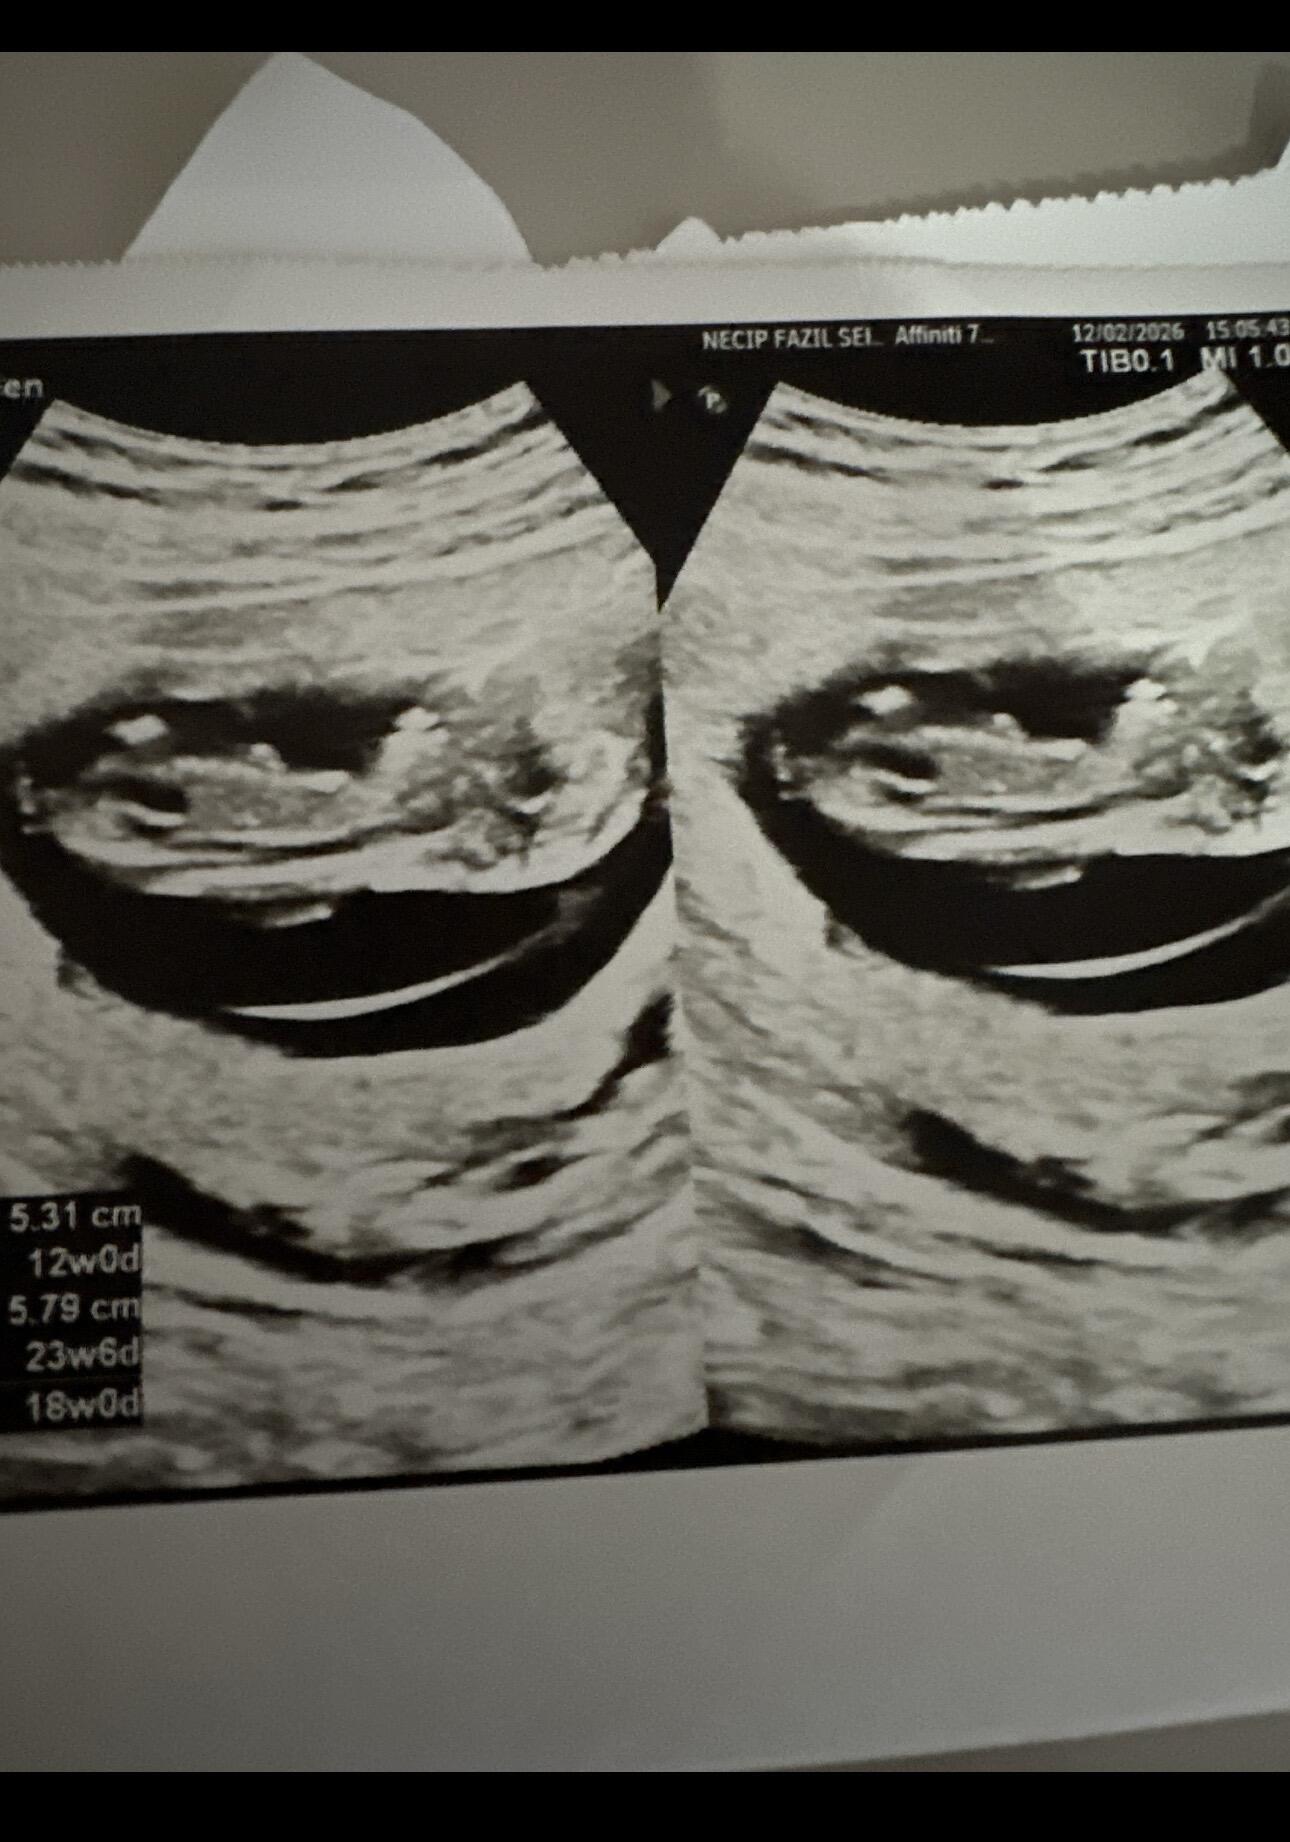

Daha net bir fotoğraf var mı keseye göre erkek bebek net var ise tekrar at bakayım canim @Sertap

Yok kuzum ya çok hareketli dedi doktor bunu zor çekti